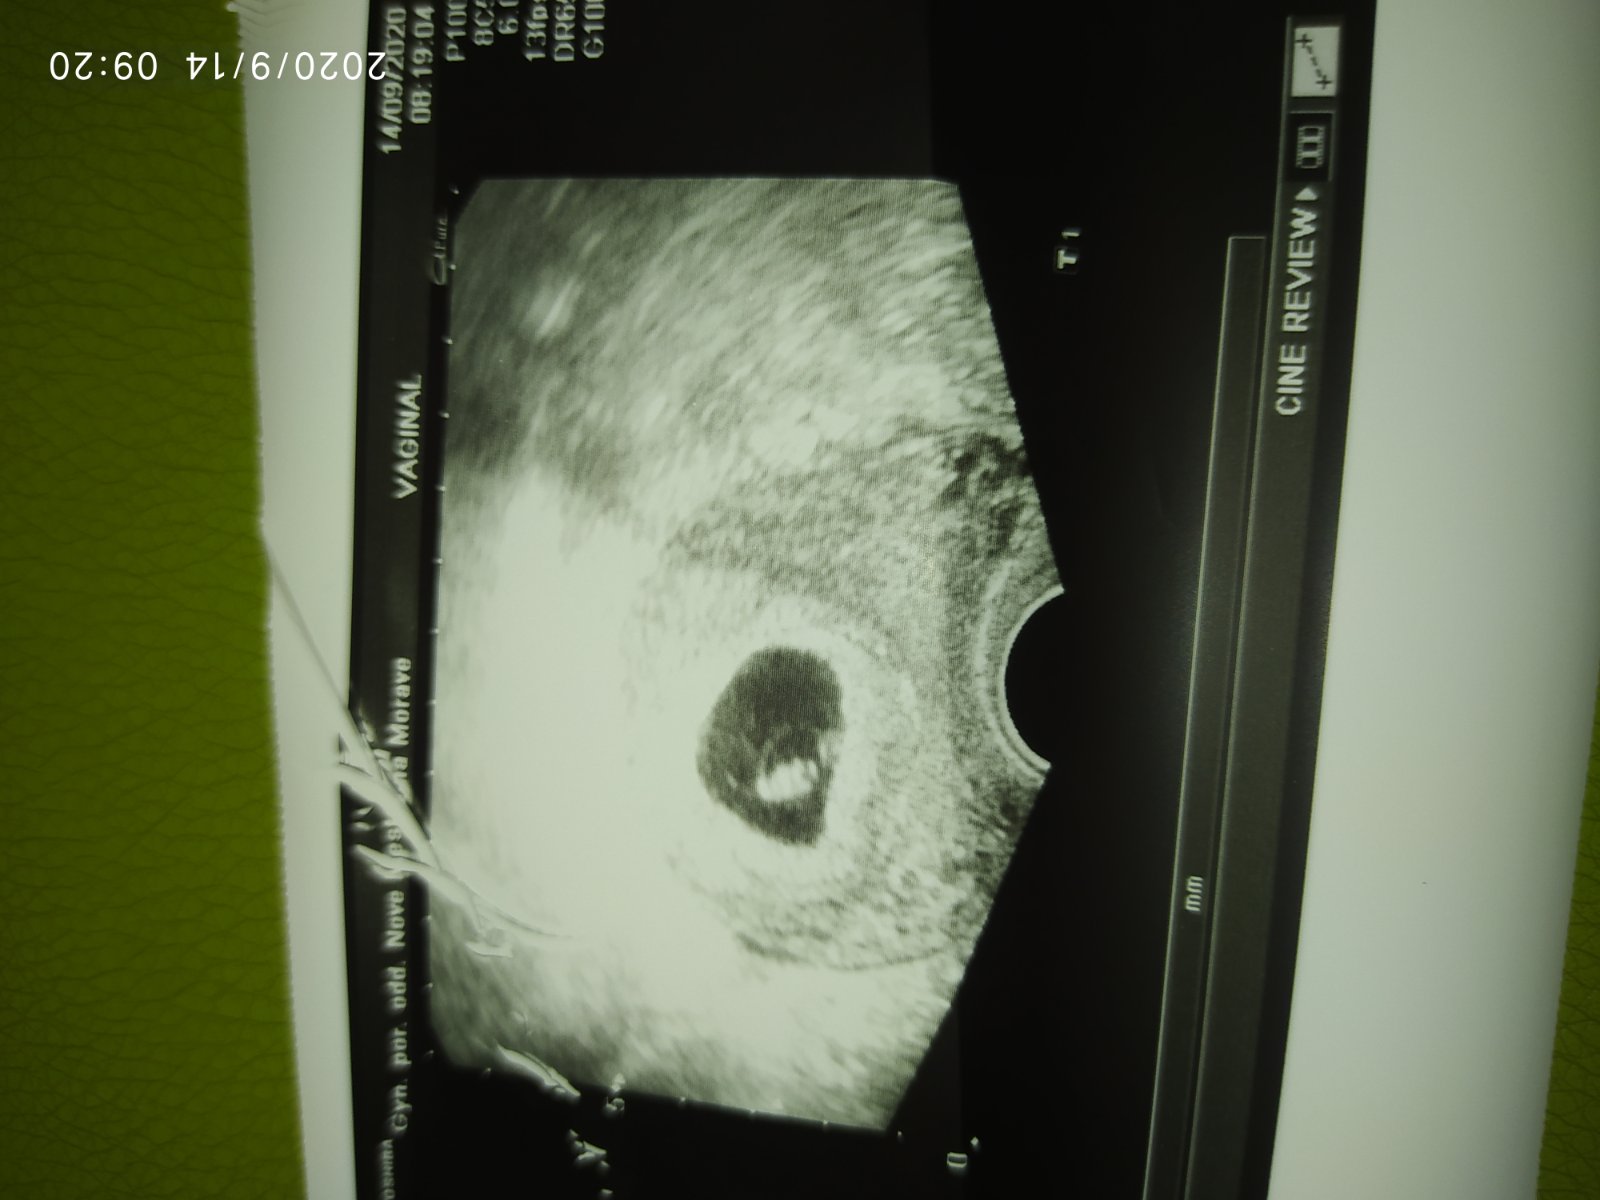

Únava hrozná. Včera zase večer přišlo špinění (světle červená krev...). Běžela jsem dnes na gyndu a nechali mě čekat hodinu a půl (to nepochopím, i obvodní mě akutně vezme hned 🤦♀️ a to jsem si dopředu volala), tam mi doktor řekl, že je to trochu podrážděné a máme se vyhnout 14 dní sexu (víc neřekl, ani mi nic nedal, prostě mě úplně odbyl...). Ale srdeční akce tam prý je, jen ještě nejde moc vidět (prý jsem měla zhubnout aby to šlo už vidět lépe a to podotýkám že teda nemám 30kg nadváhu 🤦♀️) a v úterý by to mohlo jít lépe vidět. Tak mě jen vytočil, ale snad to bude dobré. Jen bych čekala trošku více péče a empatie🤷♀️